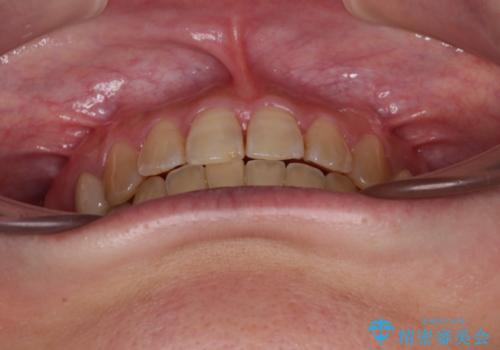

治療の期間と費用はかかりますが、初診時とは比べものにならないほど良好な状態にて治療を終えることができました。